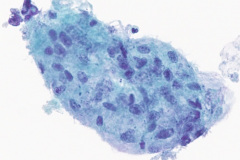

Specimen Type: Right Lower Lobe Lung Brush, Thin Prep® Non-GYN, modified Romanowsky smear, and Cellient® cell block.

Cytologic Diagnosis: Negative for malignant cells, acute inflammation, multinucleated giant cells, few poorly formed granulomas, iron pill fragments.

Cytology:

Initial diagnosis of IPA is not always readily distinguishable on cytology examination of slides. There may be a presence of a small amount of yellow-brown material on modified Romanowsky and Papanicolaou stains which without the clinical history of aspiration could easily be interpreted as non-specific artifact or other types of pigmented particles such as hemosiderin or carbonaceous particles.6 Histological examination of biopsy material is typically the gold standard for diagnosis, wherein iron pill injury is characterized by the presence of crystalline iron fibrils in the presence of necrosis or in an ulcer base.1 An iron stain such as Perls’ Prussian Blue can aid in determining the iron composition of the yellow-brown material by staining iron as a bright blue color.9 Microscopic features of the biological response to the aspiration exposure may include the presence of multinucleated giant cells, hemosiderin-laden macrophages, granulomas, and reactive atypia of squamous metaplasia. Care should be taken when assessing the Prussian Blue stain results as the hemosiderin in macrophages will also stain positively.9